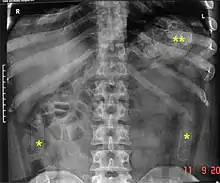

رادیوگرافی ساده از شکم یک «قاچاقچی» (حملکننده مواد) که کپسولهای دارو را نشان میدهد